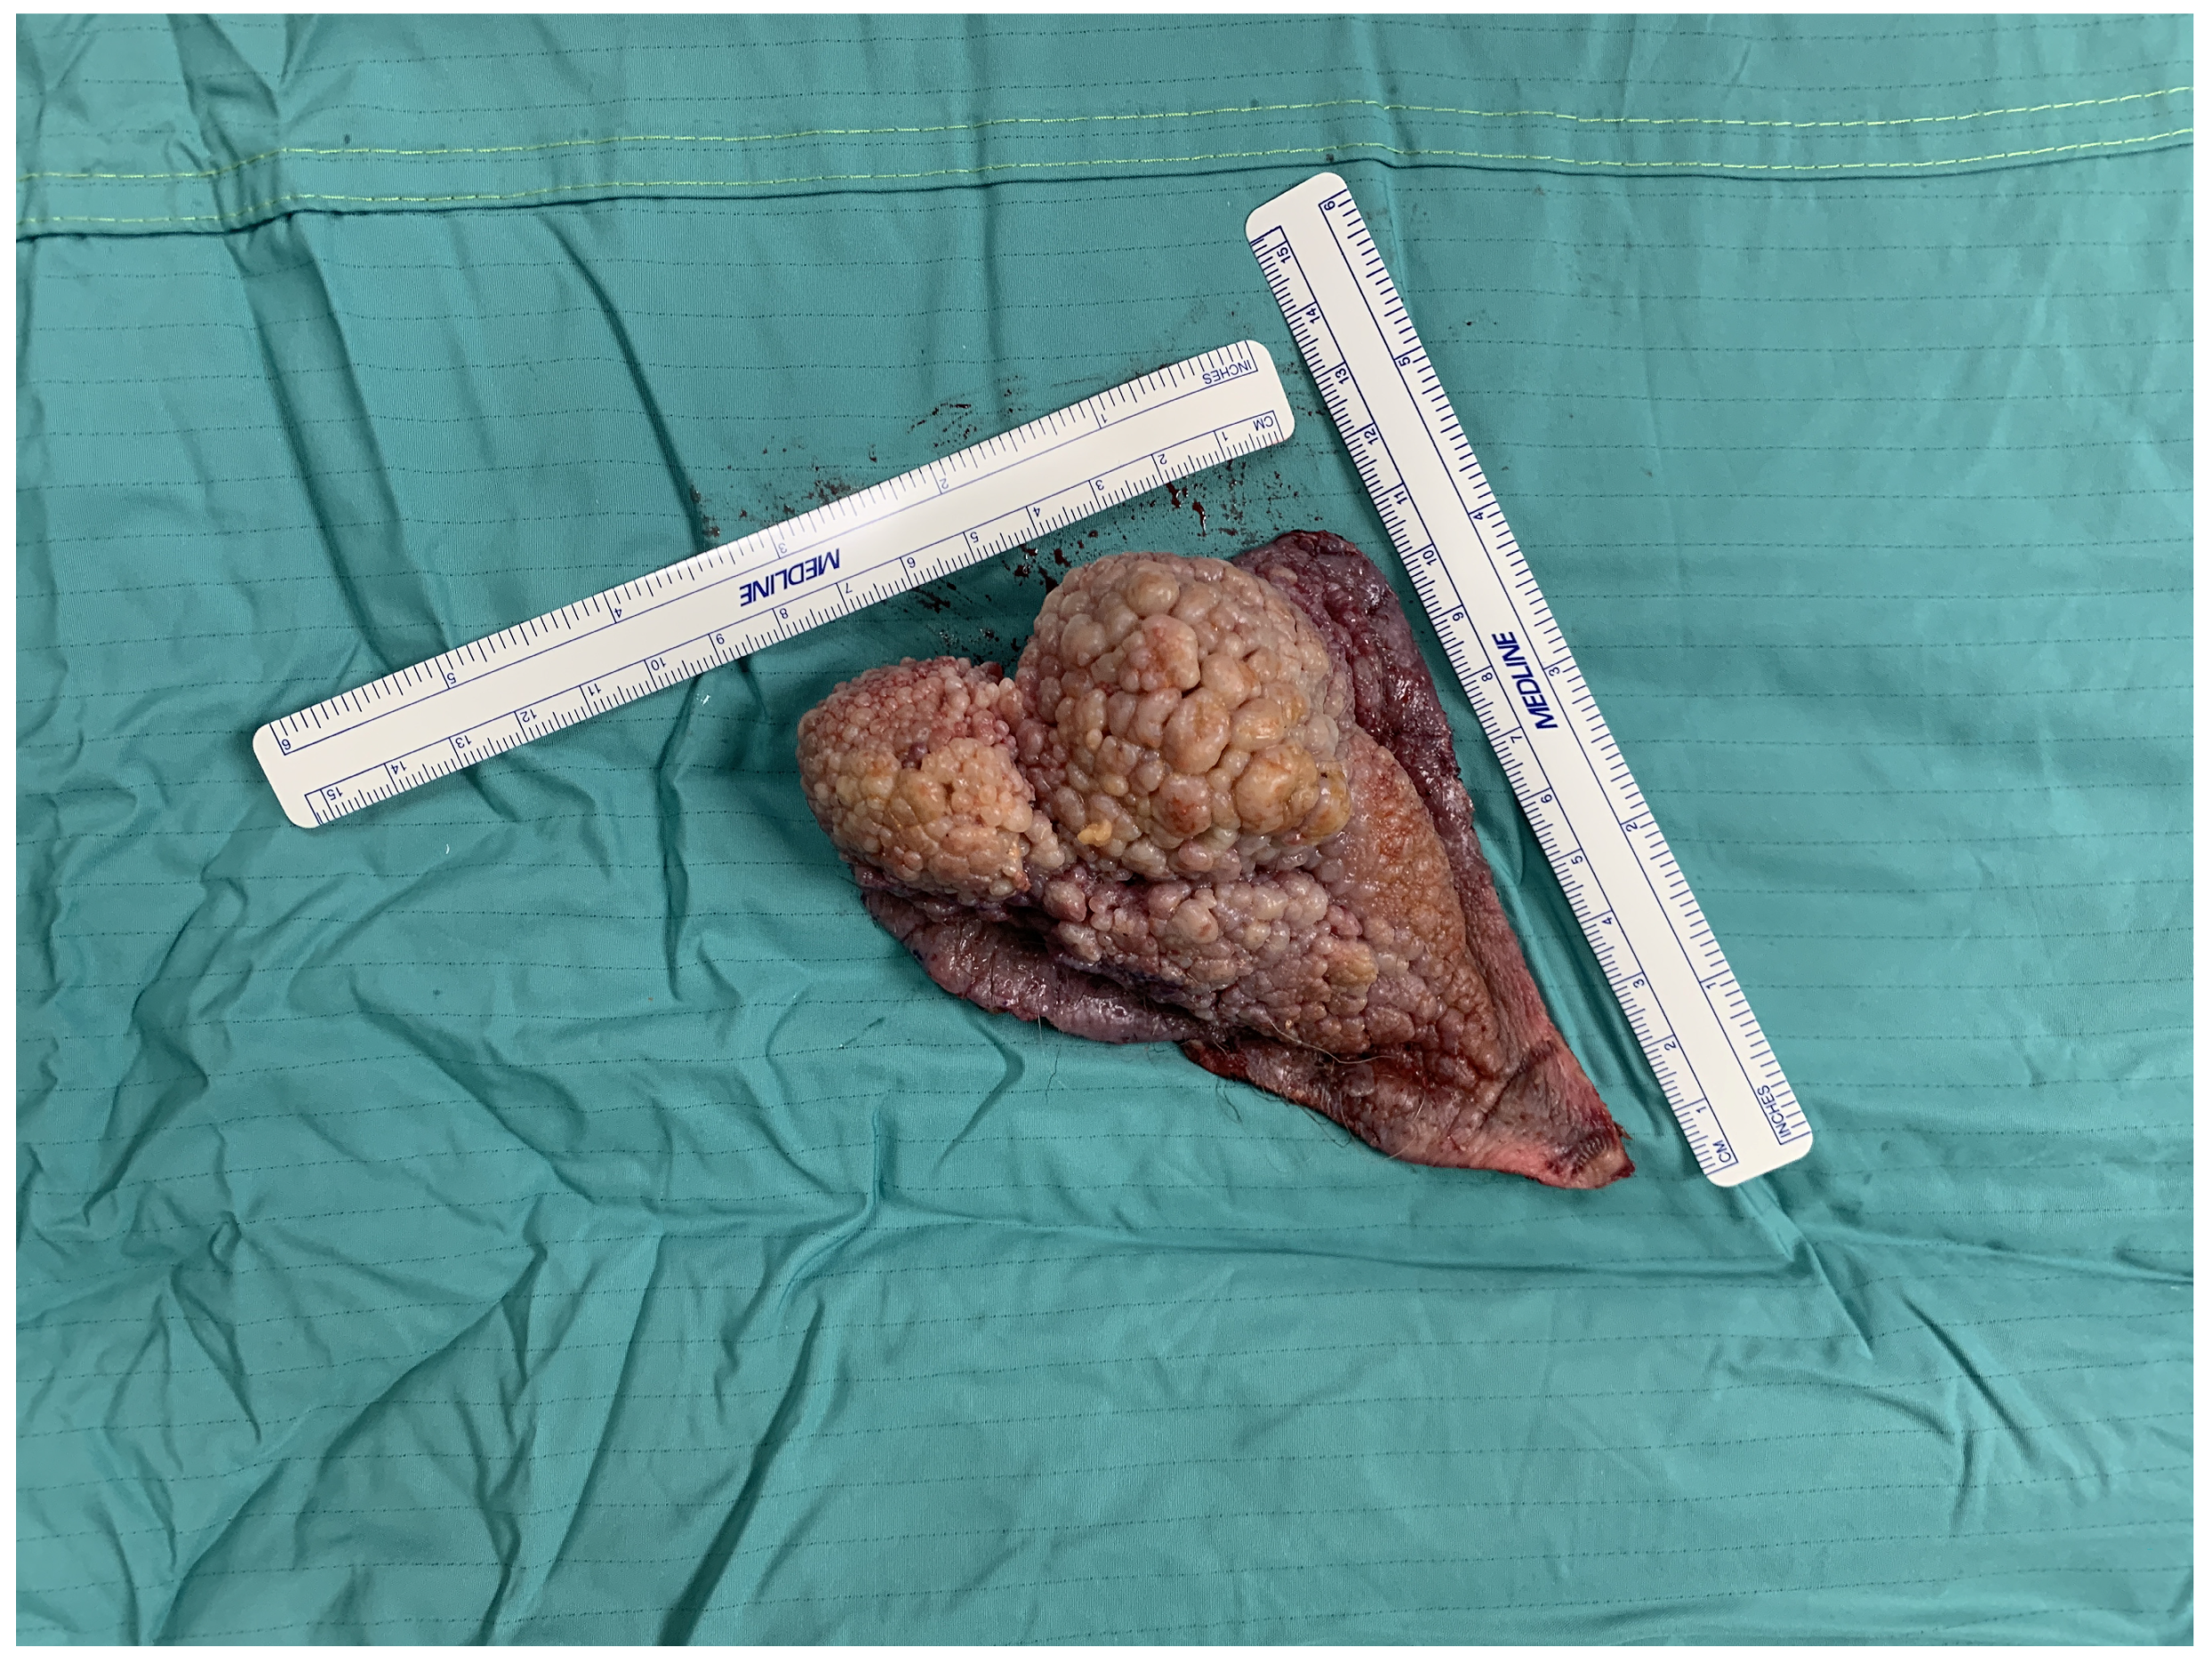

2.3. Case Presentation